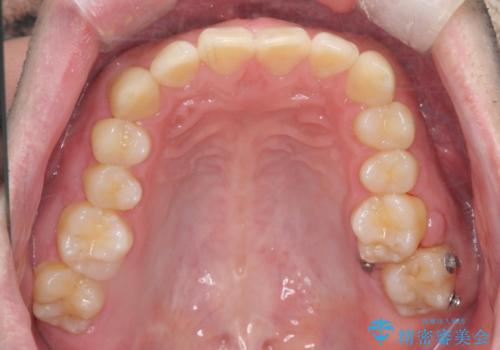

左上の奥歯がシザーバイトがありワイヤーで部分的な矯正を行い、シザーバイトを改善した後にインビザラインで全体的な矯正治療を行いました。

シザーバイトは歯と歯が噛み合っていないのでしっかり噛むように処置をする必要があります。